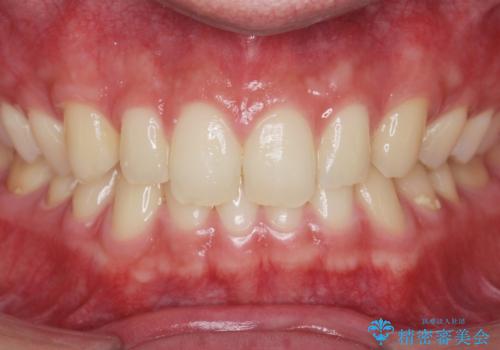

クリーニング(PMTC)掲載症例数554件

最新 クリーニング(PMTC)症例